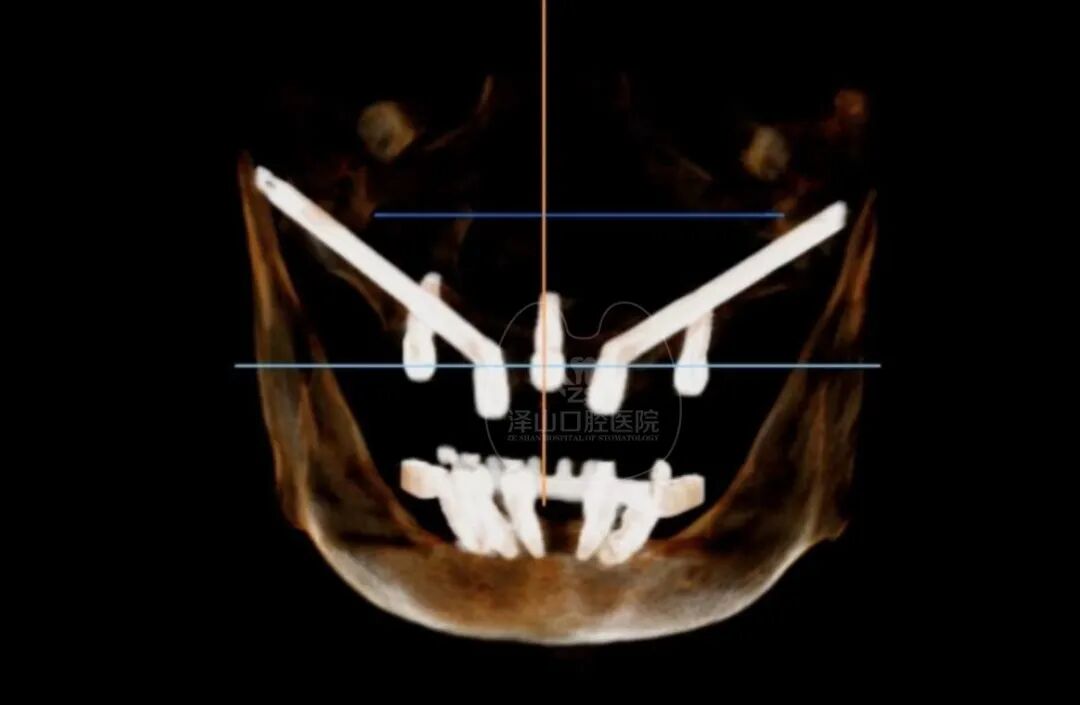

1 通过高智能数字化检查系统扫描得到口腔精准数据,同时兼顾后期修复等诸多因素进行综合考虑,量“齿”定制一种顶级高难度治疗方案——穿颧种植,帮助张阿姨恢复一口好牙! 01 什么是穿颧种植? ![]() 穿颧种植:穿颧种植被称为是当今难度较高的种植技术,指的是颧骨固定种植技术,该技术无论稳定性还是受力性都非常好,也是当今难度较高的种植技术。适用于上颌骨切除、上颌骨重度萎缩、常规内外提升都没有办法达到种植条件的无牙颌患者,通俗地被人称为“无土培栽技术”。 02 为什么说“穿颧种植” 是种植界的“珠穆朗玛峰”? 穿颧手术的关键还是在于患者剩余骨量比较少,需要做一个比较长的颧种植体,植入颧骨区。因为患者牙槽骨严重萎缩,暴露口腔颌骨区域比较少,需要医生对解剖结构比较了解,才能在有限的视野里面成功植入一个比较长的颧种植体。因此,对医生术前设计和术中的操作以及临床经验是一个比较大的考验。 03 穿颧种植和常规种植相比效果如何? 穿颧种植由来已久,国外已经开展多年。综合来看穿颧种植与常规半口全口种植远期的成功率是没有根本区别的,可能只是选择的骨头位置不太一样。在国际上来看,穿颧种植10年里面的成功率大概在97%左右。 1、感觉更舒适,更自然,坚固耐用 2、具有很好的固位效果 3、使咀嚼效率达到与自然牙媲美的程度 4、刺激骨组织,延缓颌骨的吸收与萎缩 5、不损伤邻牙,并且能有效地保护邻牙 ![]() 数字化种植牙技术是将计算机断层扫描技术(CT)、计算机辅助设计技术(CAD)和快速原型制造技术(RP)综合应用于种植手术的放心、准确的方法。 |